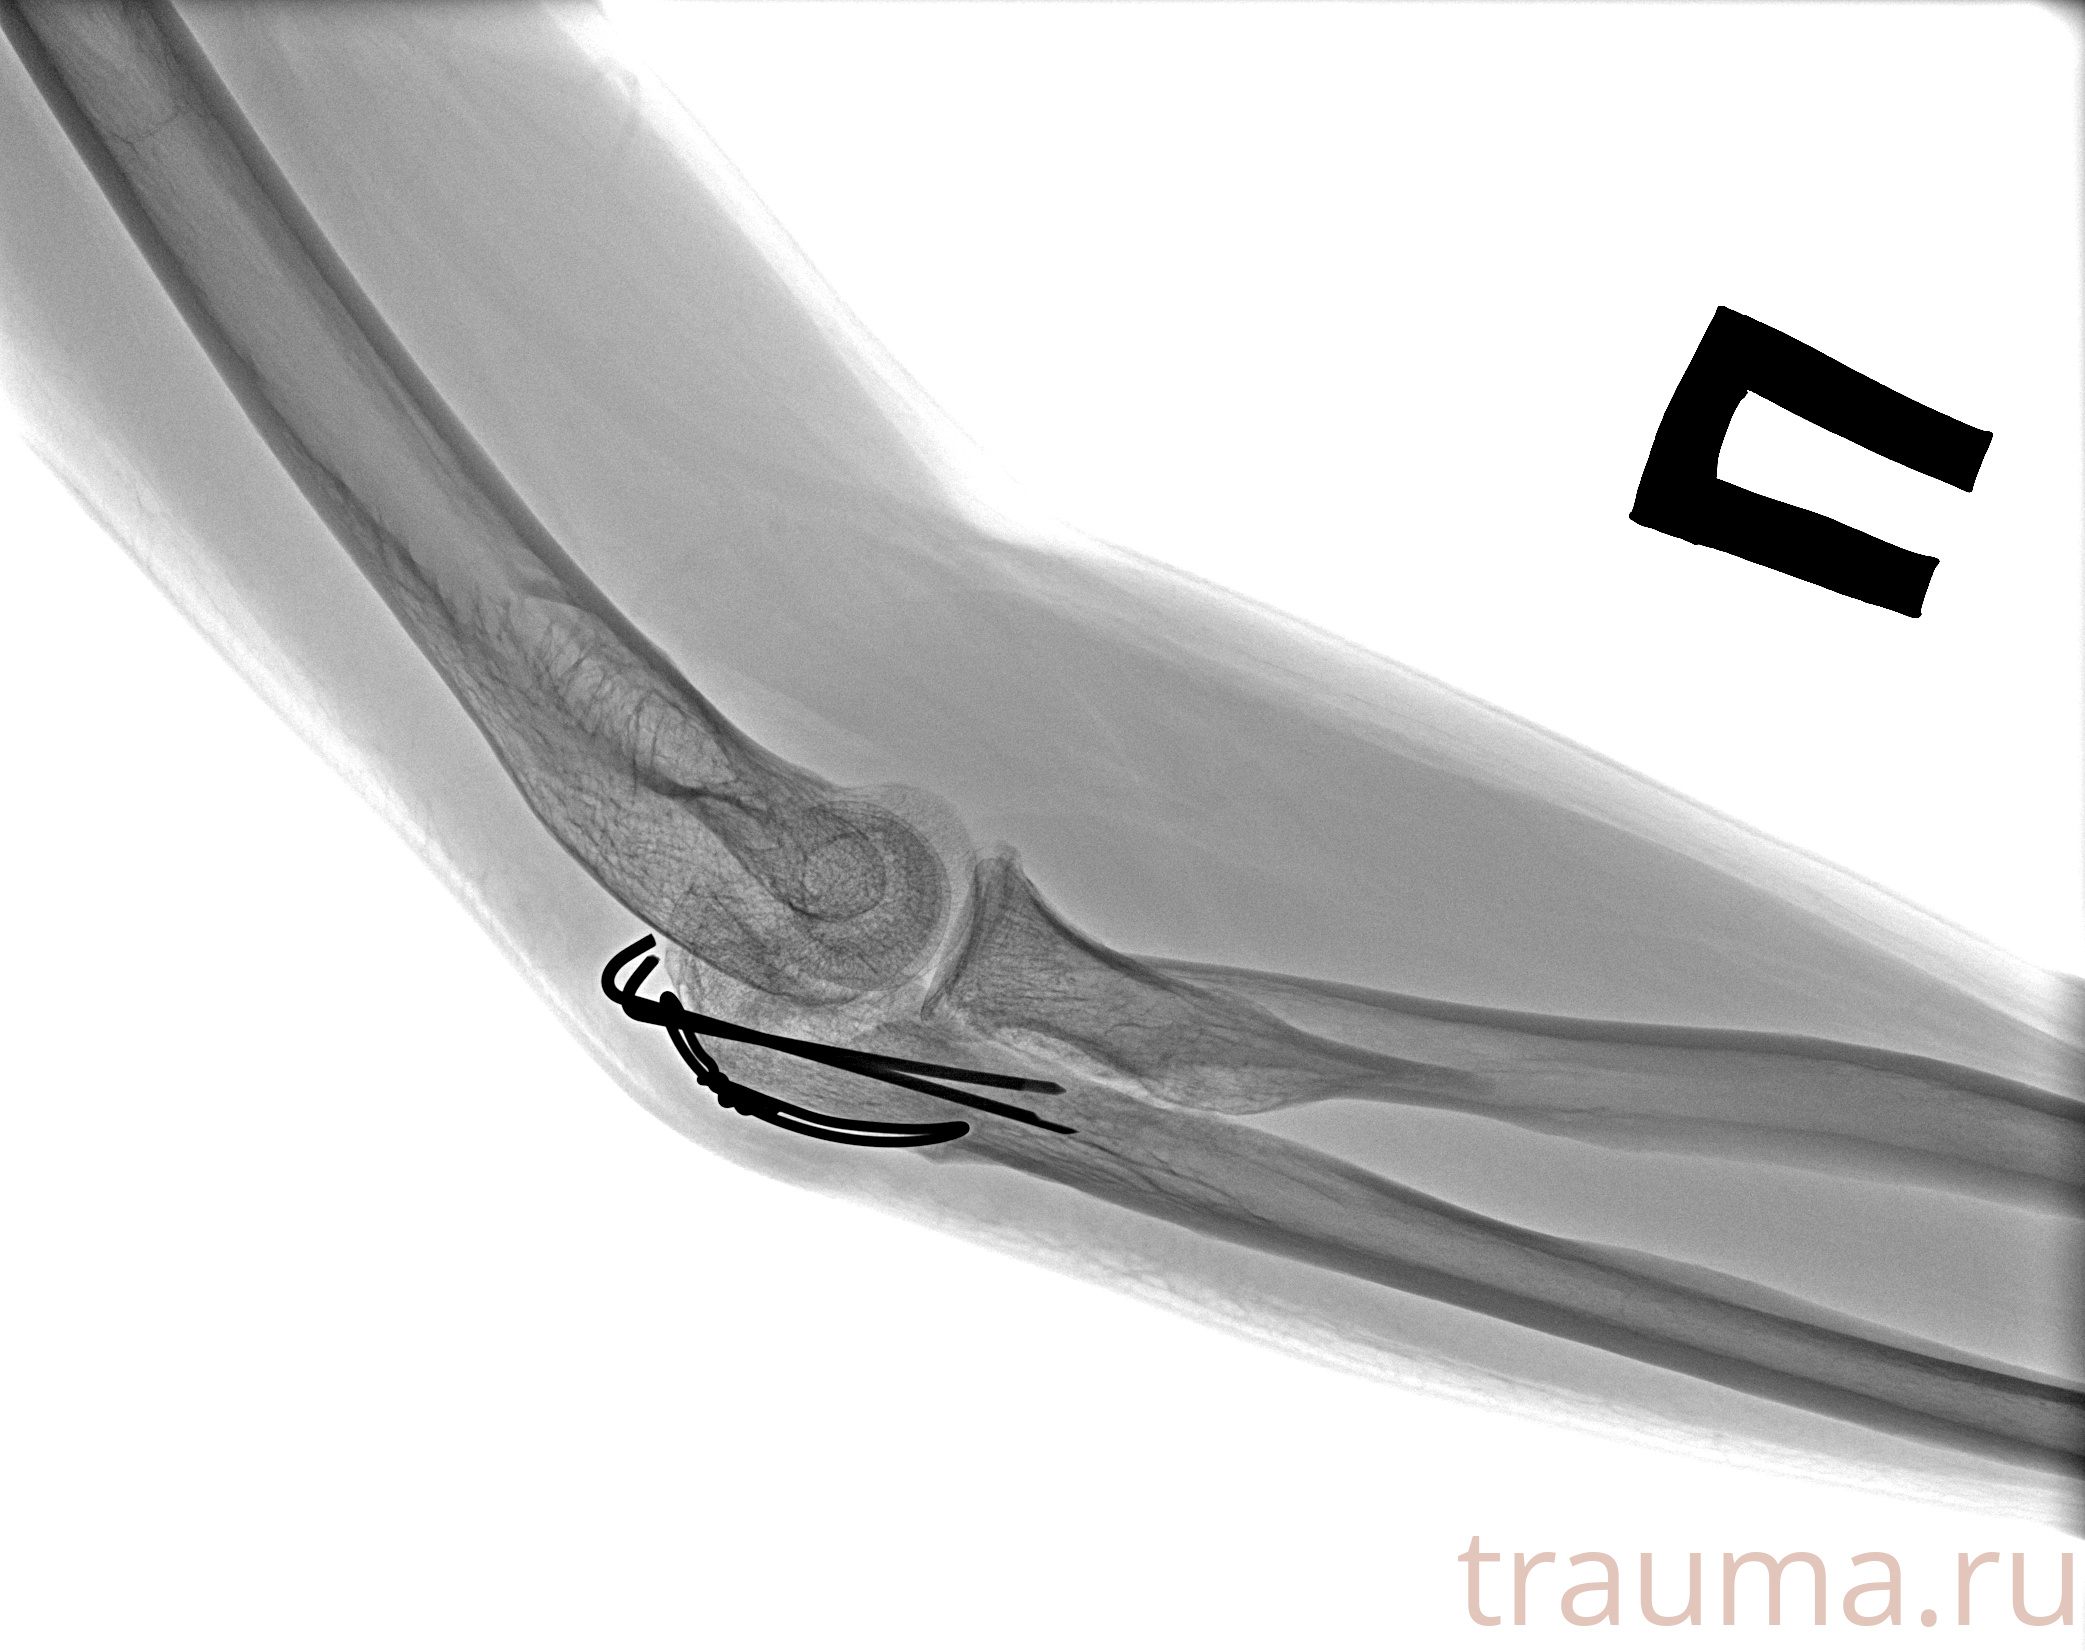

Рентген на дому: по вашему адресу приезжает врач-рентгенолог, травматолог-ортопед с мобильным рентгеновским аппаратом, проводит диагностику травмы или заболевания, делает необходимые рентгенограммы, дает рекомендации по дальнейшему лечению. Получить качественные снимки в домашних условиях возможно благодаря уникальной методике, разработанной МосРентген Центром для института  Склифосовского